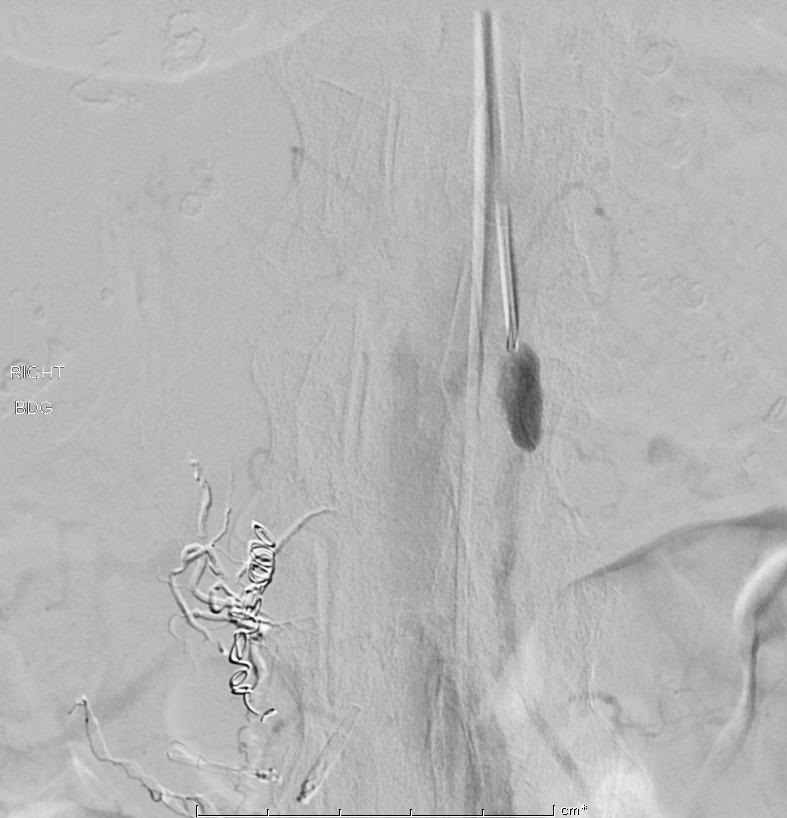

| 非食道静脉曲张消化道出血的血管内治疗围手术期相关并发症发生率大约在10%左右,包括血管造影相关并发症、血管收缩剂使用相关并发症和栓塞相关并发症和死亡。临床相关的患者基本条件如年龄和伴发疾病与围手术期相关并发症强烈相关;而操作相关围手术期并发症包括与临床结果无关的并发症和急性肠缺血并发症(<5%)。 1. 血管造影相关并发症 (1)穿刺部位相关并发症 ( Puncture site complications ) (2)CIN -造影剂肾病(Contrast-induced nephropathy:此病人人群较高 (3)其它全身并发症:心肌缺血、败血症和过敏反应 2. 血管收缩剂使用相关并发症:心律失常、血栓,心肌缺血,体液潴留(fluid retension) 3. 栓塞相关并发症[6,8] (1)肠道缺血(Bowel ischemia )/梗死:发生率0-4%;下消化道出血>上消化道出血;微粒>明胶海绵颗粒>弹簧栓子;缺血性改变大多数是自限性的。肠梗塞[5] :9%。 (2)意外栓塞:(?%)但罕见 女,74岁 多种疾病和间歇性消化道出血,红细胞标记扫描出血部位被定位在右下腹,回场末段或升结肠。早先血管造影和内视镜为阴性。两天后再次大出血。

(3)弹簧栓子释放位置不良或移位(1-3%)。

预防推式弹簧栓子释放时位置不良可选择正确直径大小或使用可脱微弹簧栓子。 (4)痉挛/夹层(2%)

(5)导管相关血栓形成(罕见) 4. 再出血 出血部位血管丰富(abundant vascular supply),缺血并发症的几率低,但潜在持续性或复发出血的几率高。上消化道出血栓塞后的再出血率为27% [1-3]。而外科术后消化道出血的再发生率也是27%。栓塞后30天再出血率为23%-45%,特别是经验性栓塞(血管造影并没有发现出血源)。上消化道出血栓塞后再出血的预测因子,临床相关最强因子是凝血障碍,操作相关的最强因子是单独使用弹簧栓子[6]。 Loffroy 等人曾综合复习了消化道出血栓塞相关并发症之再出血

反复栓塞仍然间歇性出血。 5. 死亡[6,7] (1)30天死亡率9%-31% (2)相关操作死亡率<5%